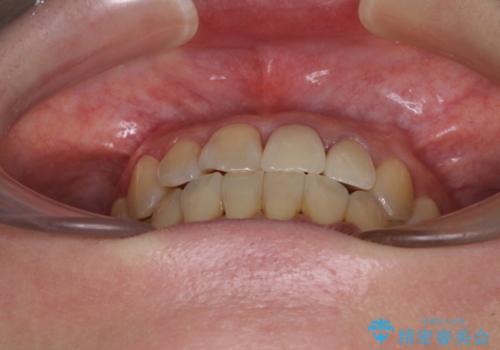

- 前歯の反対咬合により、日々強い痛みを感じているとのことで来院された患者様です。

骨格的に下顎が前方位にありますが、歯列矯正で前歯の被蓋関係を改善することができると判断されたため、インビザラインにより矯正治療を行うこととしました。

また、上顎前歯と下顎大臼歯に神経を取り除いた歯があったため、矯正治療後に、セラミッククラウンにて補綴することとしました。

前歯が内側に倒れ込む力がかかり、正常な歯ぎしりもできないため、非常に負担のかかりやすい咬み合わせでした。

矯正治療中に上顎前歯が下顎前歯を乗り越える際は、前歯でしか咬めない状況が続くため、食事など不便を感じましたが、治療後には前歯の痛みもなくなり、安定した咬み合わせとなりました。